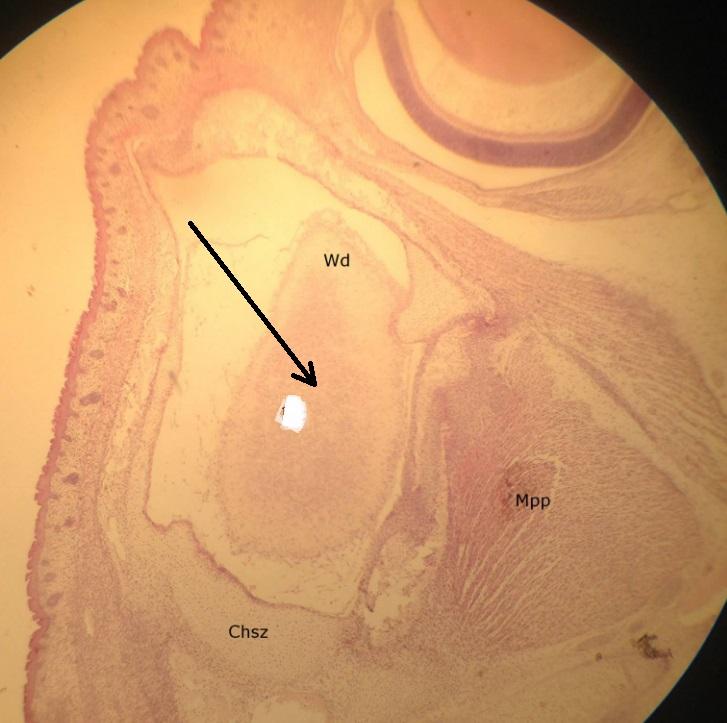

Pytanie 357

zawiązek oka (preparat rozwojowy z głowy szczura, okolice zawiązka mózgu)